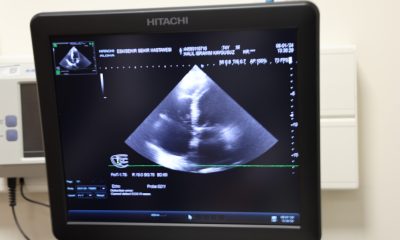

Erken tanının önemini vurgulayan Dr. Yurtman kan testleriyle kolesterol, şeker ve trigliserit değerlerine bakılabileceğini; efor testiyle de kalbin performansının görülebileceğini ifade etti. Boyun ve bacak damarlarını gözden geçirmek için ultrason (doppler); damarların içini üç boyutlu görmek için ise BT anjiyo yapılabileceğini sözlerine ekledi.